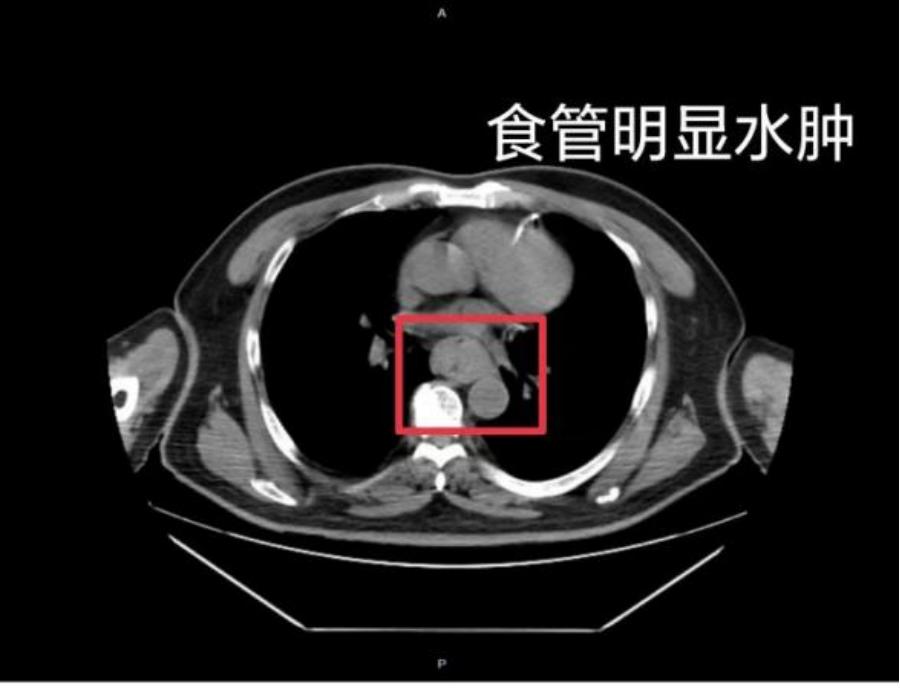

據2024年12月報道,家住江蘇常州的蔡先生在煮好泡麪後,未等其冷卻便匆忙食用,隨後出現喉嚨及食管劇烈灼痛。起初他並未重視,但半個小時後,“胸骨後”疼痛依然持續。爲了緩解不適,他嘗試嚥下一口硬米飯,結果發生劇烈嘔血,並出現休克症狀,家屬見狀立即將他送往醫院。

胃鏡檢查發現,蔡先生的食管黏膜出現大面積糜爛、剝脫,創面充血嚴重。經過抗炎、止血、保護消化道黏膜、輸血等治療,他的病情得到好轉。